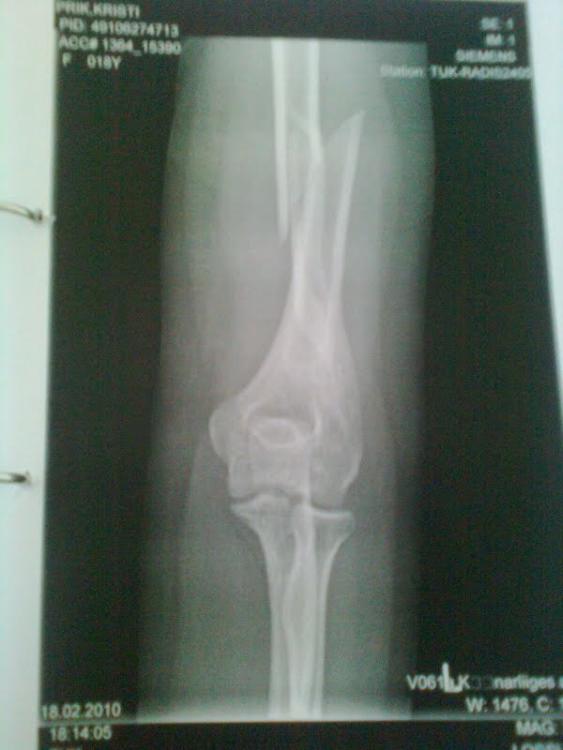

Murdsin 2010 jaanuaris oma küünarvarreluu päris pooleks, käisin lõikusel ja pandi kruvid sisse. 2014. suvel võeti enamus kruvid välja, 2 jäid veel sisse (paiknesid liiga närvi lähedal ja nende eemaldamine oleks olnud ohtlik).